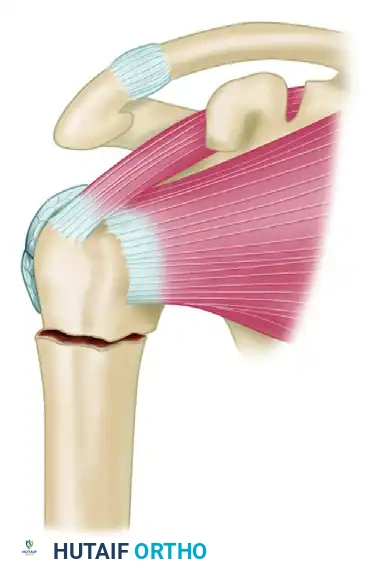

Nonunions of the proximal humerus present a unique biomechanical challenge due to the multidirectional deforming forces exerted by the rotator cuff musculature. The proximal fragment is often osteopenic, making standard screw purchase precarious and leading to a high risk of hardware pullout.

Step 1: Identification of the nonunion site. The proximal fragment is subjected to superior displacement by the supraspinatus, while the humeral shaft is pulled medially by the pectoralis major.

Step 2: Following debridement of the nonunion and bone grafting, a T-plate or proximal humeral locking plate is applied to the lateral aspect of the humerus to provide a rigid buttress.